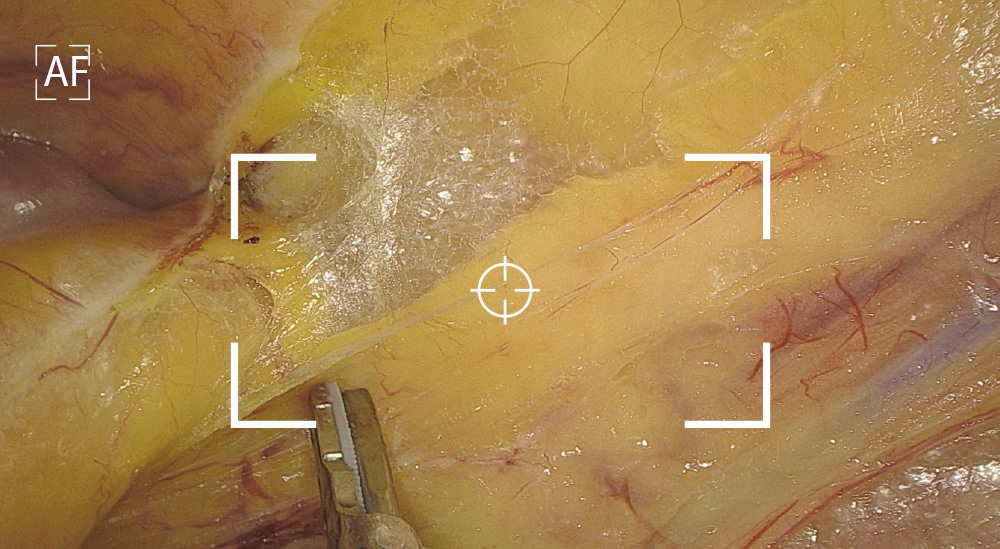

Integrated Auto And Manual Focus

AutoFocus and high quality image achieved with one touch